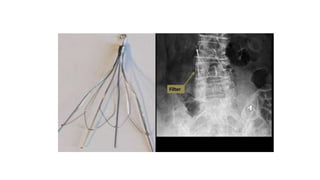

Inferior Vena Cava filter: It is a type of vascular filter, a medical

pulmonary emboli (PEs).

Continue Inferior Vena Cavafilter: It is a type of vascular filter, a medical device that is implanted by interventional radiologists or vascular surgeons into the inferior vena cava to prevent life-threatening pulmonary emboli (PEs). Indications: • Pulmonary embolism with contraindication to anticoagulation. • Recurrent pulmonary embolism despite adequate anticoagulation.